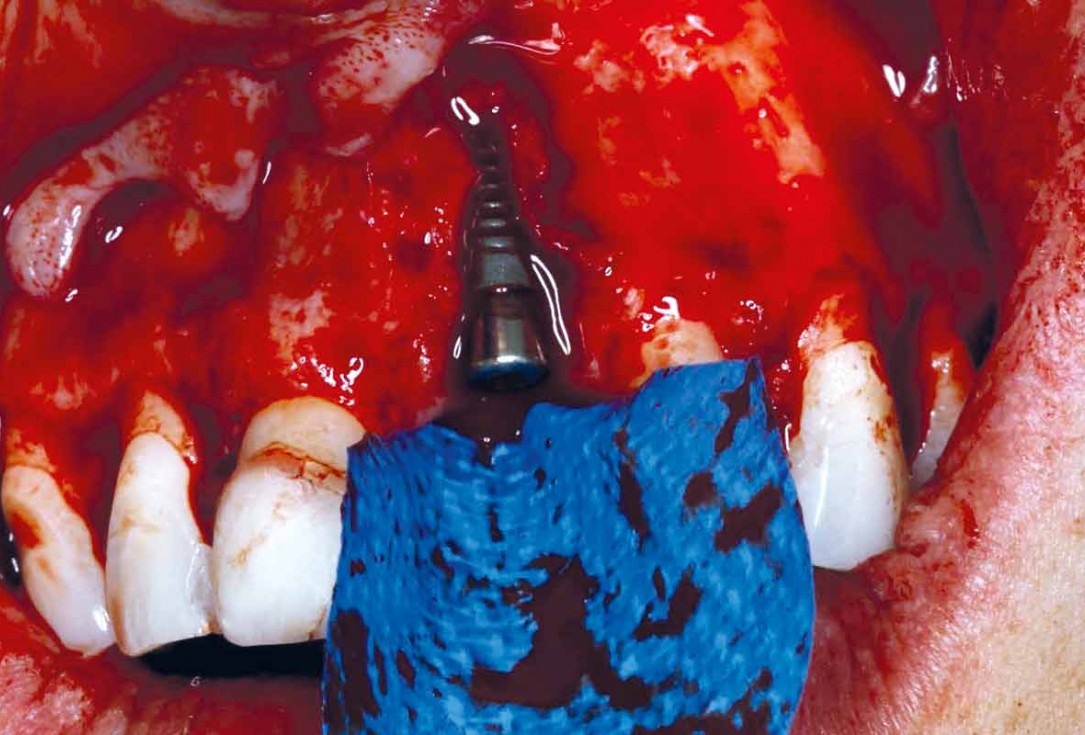

Implant placement and bone augmentation in the aesthetic zone using maxgraft® and permamem® - Dr. A. Puišys

Implant placed in the deficient site. permamem® in place for covering.

Initial situation – Treatment plan: Replace the adhesive upper left central incisor bridge with a dental implant